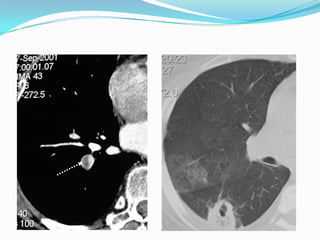

Embolie pulmonaire:

 Dl brutale basithoracique, augmentée par respiration,

s’accompagne d’1 dyspnée, angoisse parfois syncope ou état

de choc dans embolie massive.

   Contexte évocateur: mauvais état veineux, alitement

prolongé, intervention chirurgicale récente, thrombose

veineuse périphérique.

   ECG: nl, tachycardie sinusale, BBD, aspect S1Q3.

   Gaz du sang: hypoxie, hypocapnie.

   Radio pul: nl, atélectasie en bande basale droite.

   Dg confirmé par TDM spiralé thoracique, angiopul ou

mieux scintigraphie pulmonaire.

   Le trt repose sur anticoagulation efficace.